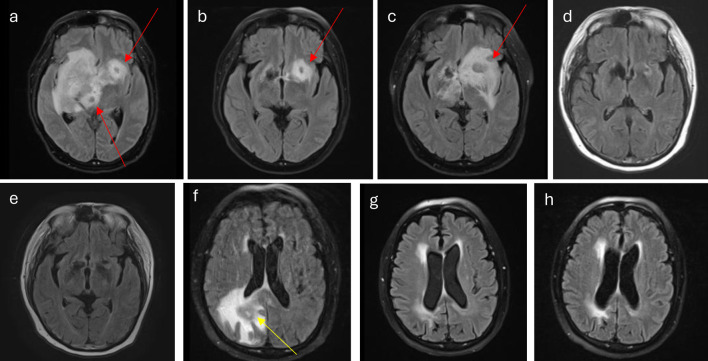

Central nervous system lymphoma (CNSL) is an aggressive disease with limited well-studied options for treatment, especially refractory treatment. First-line treatment usually includes high-dose methotrexate (HD-MTX) for induction and either autologous stem cell transplantation or whole-brain radiation therapy (WBRT) as consolidation. However, WBRT can result in significant neurotoxicity, so the use of focal radiation (i.e., gamma knife-stereotactic radiosurgery (GK-SRS)) of varying doses and fractions has been proposed. In the case of refractory disease, chimeric antigen receptor (CAR) T-cell therapy has begun to be used clinically, but patients with CNS involvement were left out of key approval trials. Here, we present a case of a 62-year-old patient with refractory secondary CNSL (SCNSL) previously treated with WBRT who was successfully treated with a combination of CAR T-cell therapy and GK-SRS.